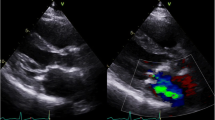

Valvular heart disease is present in as many as 81% of patients with RACD [14]. The left-sided valves are involved to a far greater extent than right-sided valves, and valvular manifestations may be either stenotic or regurgitant. Radiation may result in damage to valve leaflets, including fibrotic thickening, retraction, and calcification, and perivalvular structures including the annulus, subvalvular apparatus, and aortomitral curtain (AMC, Fig. 1). Indeed, thickening and calcification of the AMC is a hallmark feature of RAVD and is an independent predictor of adverse longer-term outcomes in these patients [15].

Echocardiography is the most common imaging modality used in screening, diagnosing, and monitoring RAVD [18]. Features of RAVD on TTE include biventricular systolic and diastolic dysfunction, involvement of multiple valves, wall motion abnormalities, prominent calcification, and pericardial disease. One should be cognizant of the TTE features of constrictive physiology when RAVD is suspected, including biatrial enlargement, an early diastolic septal bounce, pericardial thickening and calcification, and plethora of the inferior vena cava and hepatic veins with increased respiratory variation [1•]. The earliest manifestation of RAVD involves progressive valvular retractions and regurgitation, which typically occurs within the first 10 years following treatment [8••]. This is followed by progression to fibrotic thickening, calcification, and stenosis, which occurs ~ 2 decades after XRT [1•,18]. Again, progressive thickening and calcification of the AMC is a hallmark feature [15]. Although TTE provides sufficient information for screening and diagnosis and to inform management in the vast majority of cases, transesophageal echocardiography (TEE) may provide further diagnostic fidelity. However, one must be cautious when performing TEE in RACD due to the possibility of XRT-associated esophageal injury.